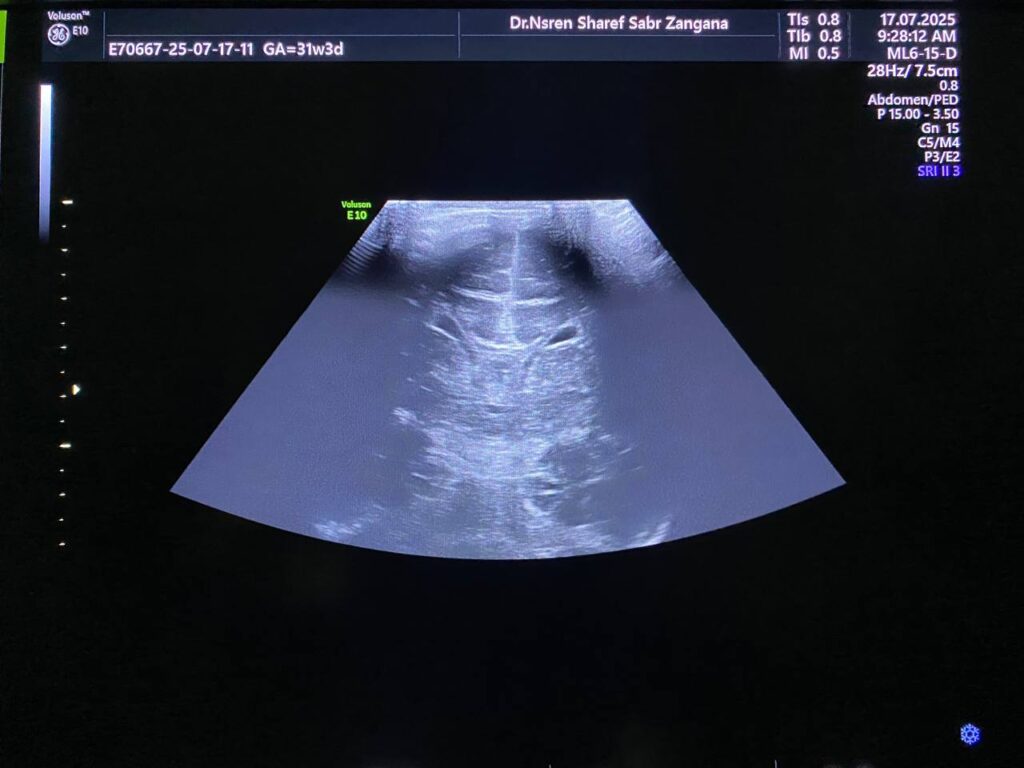

Mild hydrocephaly , maximum diamter of the posterior atrium of the lateral ventricles 16mm

Also mild dilated Third ventricle diamter 4.7mm , no dilated 4th ventricle seen , mostly due to mild stenosis at Sylvuis aqueduct

Associated with presence of of heterogenous mass 10x6mm , extruded from the brain tissue in the occipital region , mostly encephalocele